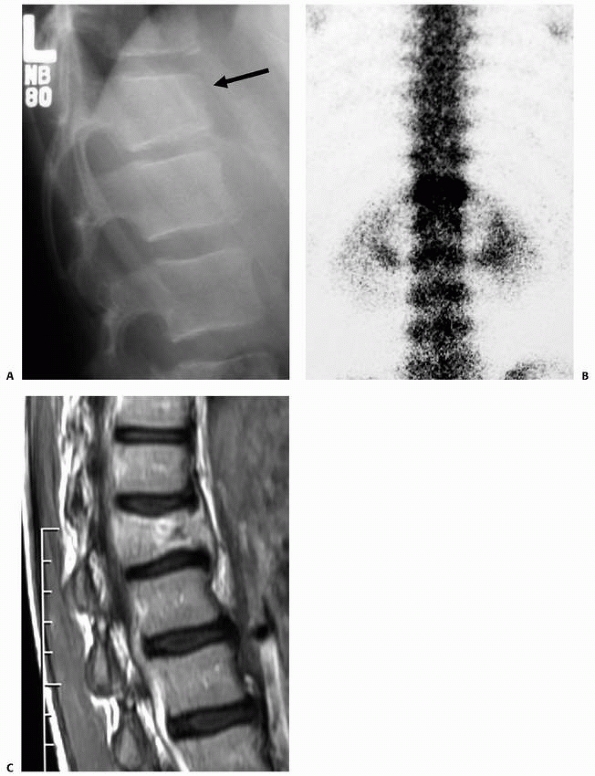

children and adolescents to a degree that predisposes them to

insufficiency fractures that are most often compression fractures (Fig. 19-8).

Multiple-level fractures are more frequent in this setting, and

problematic kyphosis may develop. Differentiating new from old

fractures can be difficult if serial radiographs are not available. A

thoracolumbosacral orthosis (TLSO) for a period of time longer than

typically used for simple compression fracture healing may be necessary

to prevent progressive kyphosis, though treating the primary cause of

the osteopenia is critical to maintaining normal alignment in such

cases. An endocrinologic evaluation and assessment of bone density by

dual energy x-ray absorptiometry are advised.

![]() |

FIGURE 19-8 A.

Lateral radiograph demonstrating what appears to be a routine compression fracture. The patient did not have a significant history of trauma; however, pain was present and a bone scan was obtained to further evaluate this site. B. The bone scan demonstrated markedly increased uptake, confirming an acute process and prompting additional study. C. An MRI was obtained, which demonstrated loss of height and a lesion within the anterior aspect of the vertebral body, which was later confirmed to be an infectious process. |